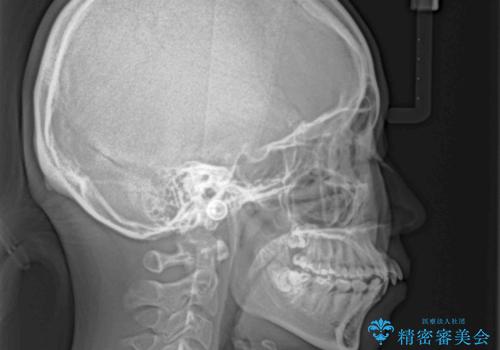

- 前歯のデコボコと突出感を気にして来院された患者様です。

上下左右第一小臼歯4本を抜歯して、積極的に口元を引っ込めるよう、ワイヤー装置にて矯正治療を行うこととしました。

口の閉じにくさが改善され、横顔のシルエットも大幅に改善されました。